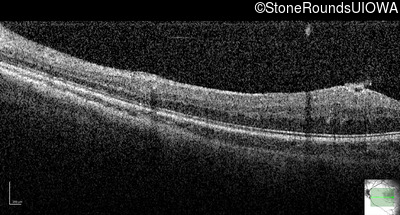

Optical Coherence Tomography - Right - 20/2000

Exemplar / OCT Stack